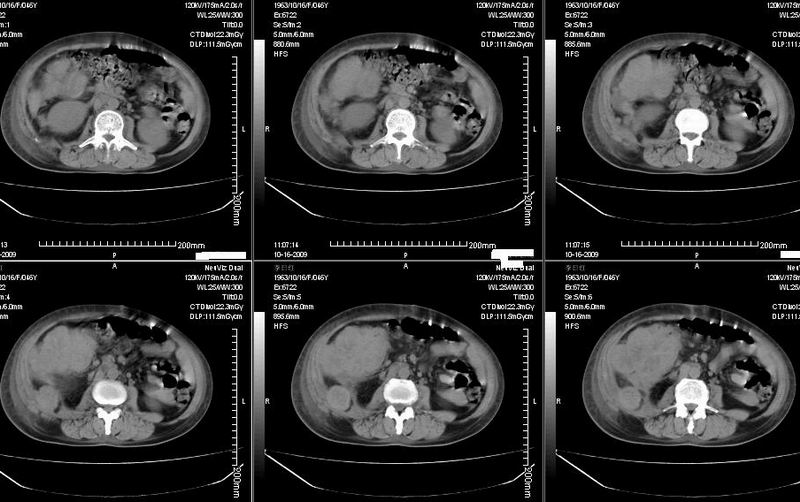

女:46y:一年前宫颈癌术后,现右下腹抚及肿块。

考虑宫颈癌术后复发周边侵犯/右中下腹及双侧腹股沟淋巴结转移。